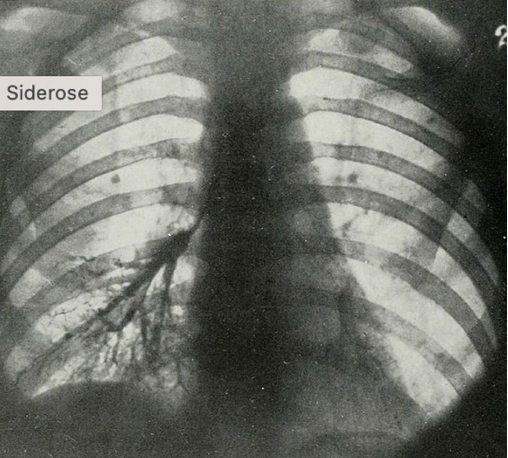

Siderose

- Agente: Óxidos de Ferro (soldadores).

- Características: Depósito de ferro nos macrófagos (siderófagos). Geralmente benigna e assintomática (forma pura), a menos que haja coexposição à sílica (Siderossilicose).